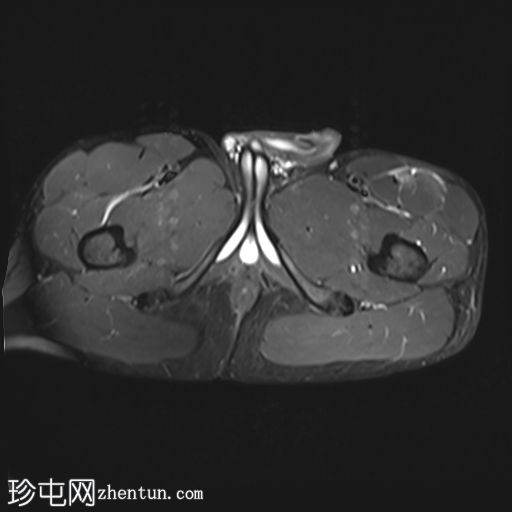

轴位

T1加权像

股直肌近端和中段前外侧可见一水肿性高信号影,长约15厘米,宽约3厘米。肌纤维轻度分离,但未见撕裂。肌内未见积液;在相邻肌间隙可见一条细小的液线环绕肌肉,延伸至近端肌腱交界处。

股直肌中段的间接肌腱轻度增厚,伴有肌腱周围水肿,提示2B级拉伤。但肌腱保持连续性,骨性附着良好,未见撕裂。